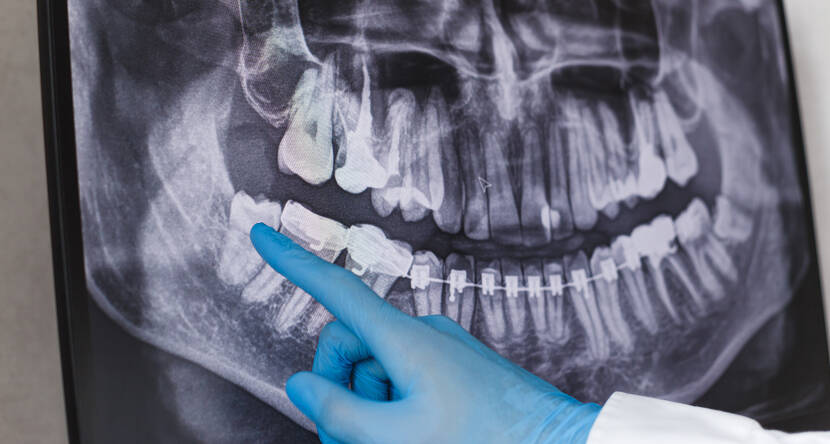

事前の詳細な診断

最先端の診断機器を用いて、事前に詳細な診断を行い、患者さま一人ひとりに最適な治療計画を立てます。

診察・カウンセリング

レントゲンやCT撮影を行い、親知らずの位置や状態を確認します。

患者さまには、抜歯の必要性やリスクを説明し、不安を解消いたします。